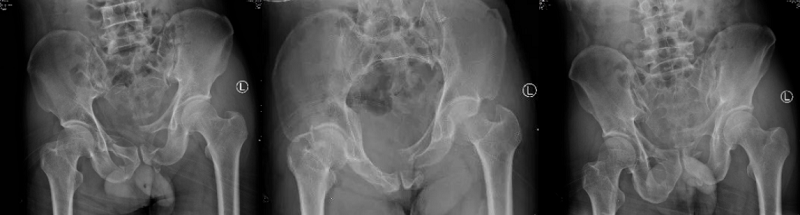

術(shù)前X線片

手術(shù)中

術(shù)后X線片